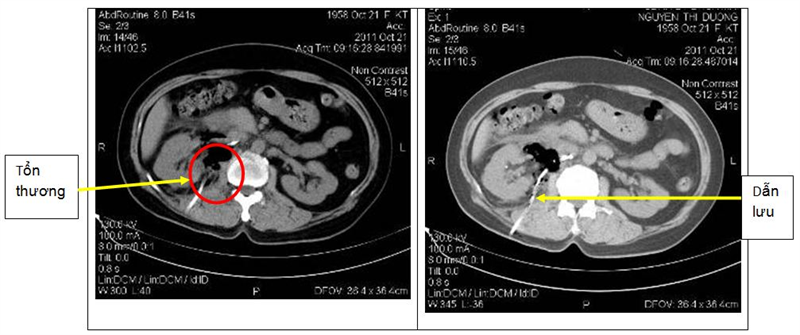

Ngày 20 tháng 10 năm 2011: tiến hành sinh thiết u lần 2 vào tổn thương sau phúc mạc lấy ra được 300ml dịch vàng chanh

Đặt stent dẫn lưu vào khối u, và bơm Betadin 10% vào khối u, lưu ống dẫn lưu.

Trong và sau thủ thuật bệnh nhân ổn định.

Sau 24 giờ tiến hành chụp CT ổ bụng đánh giá thấy hình ảnh dẫn lưu đặt đúng vị trí khối tổn thương u, có hình ảnh khí trong khối tổn thương.

Bệnh nhân được tiến hành rút ống dẫn lưu sau 24 giờ: trong 24 giờ qua sonde dẫn lưu lượng dịch ra thêm 20ml dịch vàng chanh